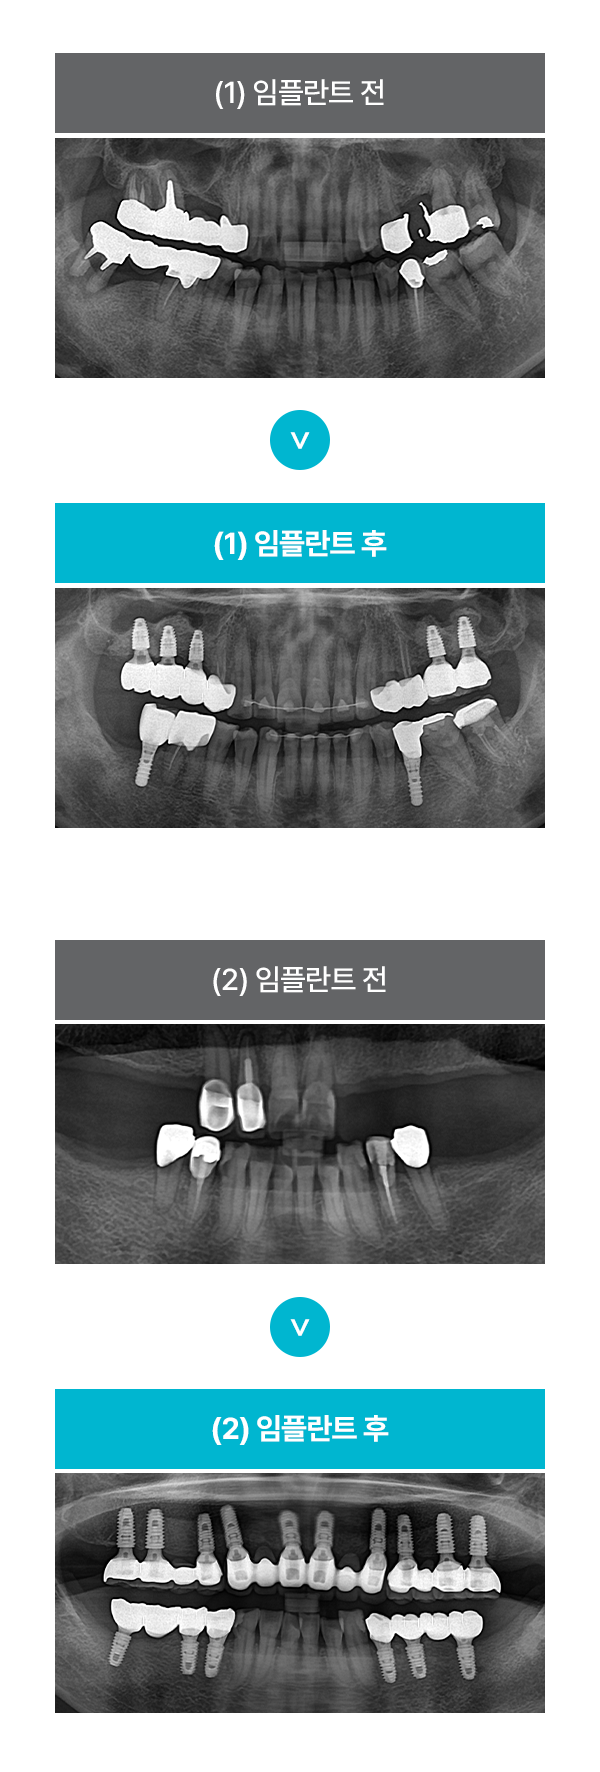

ÀÓÇöõÆ® Ä¡·á »ç·Ê